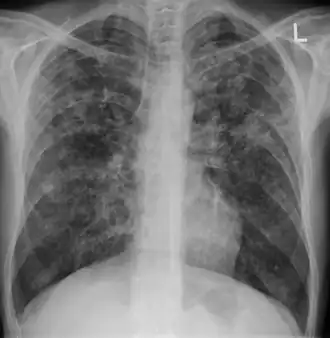

| Chest X ray showing miliary tuberculosis | |

Miliary tuberculosis is a form of tuberculosis that is characterized by a wide dissemination into the human body and by the tiny size of the lesions (1–5 mm). Its name comes from a distinctive pattern seen on a chest radiograph of many tiny spots distributed throughout the lung fields with the appearance similar to millet seeds—thus the term "miliary" tuberculosis. Miliary TB may infect any number of organs, including the lungs, liver, and spleen.[2]

Testing for miliary tuberculosis is conducted in a similar manner as for other forms of tuberculosis, although a number of tests must be conducted on a patient to confirm diagnosis.[3] Tests include chest x-ray, sputum culture, bronchoscopy, open lung biopsy, head CT/MRI, blood cultures, fundoscopy, and electrocardiography.[9] The tuberculosis (TB) blood test, also called an Interferon Gamma Release Assay or IGRA, is a way to diagnose latent TB. A variety of neurological complications have been noted in miliary tuberculosis patients—tuberculous meningitis and cerebral tuberculomas being the most frequent. However, a majority of patients improve following antituberculous treatment. Rarely lymphangitic spread of lung cancer could mimic miliary pattern of tuberculosis on regular chest X-ray. [14]

A case of miliary tuberculosis in an 82-year-old woman:

-

X-ray, 22 days after onset, showing extensive bilateral reticulo-nodular infiltrates -